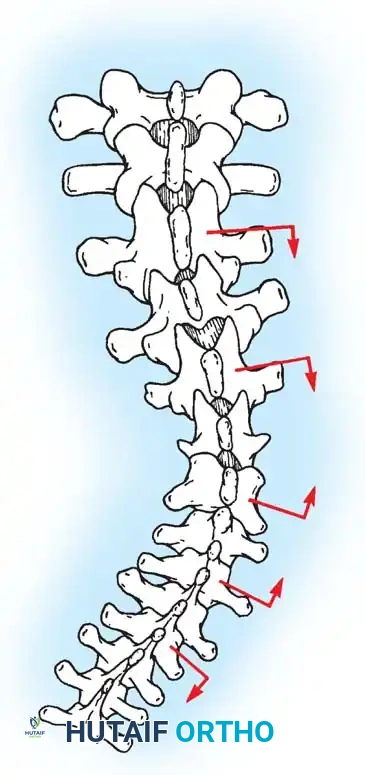

Biomechanics of Bone Grafting

Bone graft incorporates most effectively under compressive loads and is biologically disadvantaged in environments of distraction. Therefore, in scoliosis correction, if autogenous bone is limited, it should be preferentially concentrated on the concave side of the curve, which is subjected to compressive forces, rather than the convex side, which experiences tension. Furthermore, the farther the fusion mass is placed from the instantaneous axis of rotation, the more effectively it will neutralize movement across that axis.